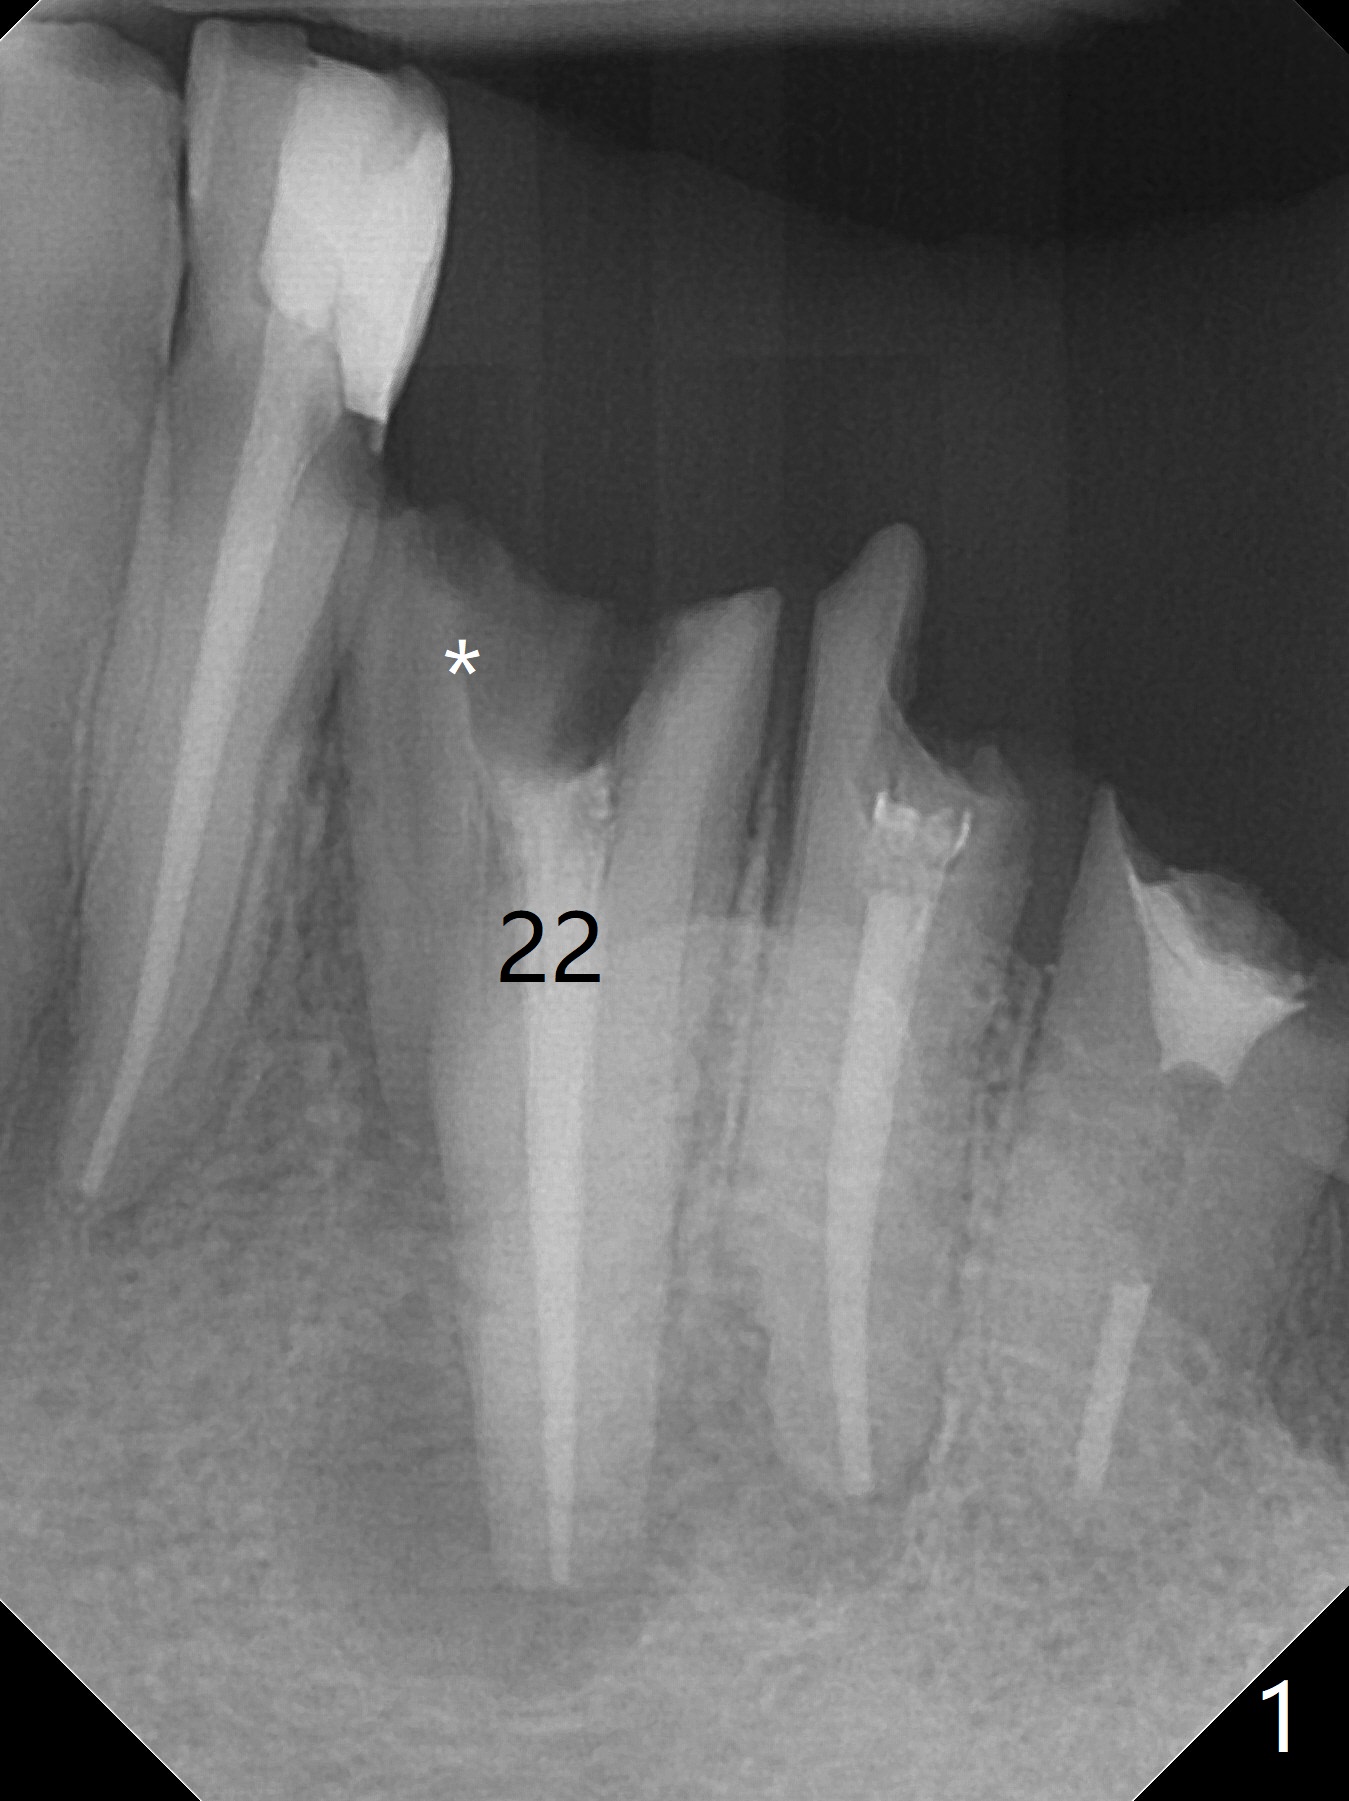

A 61-year-old man has poor dentition (#7 10), requesting extraction of the tooth #22 with root split (Fig.1 *). CT taken 1.5 years earlier (before crown fracture) shows missing buccal plate (Fig.2 B). After extraction, a smallest, longest 2-piece implant (3.8x18 mm) will be chosen to gain ~ 3 mm apical native bone for primary stability; to obtain a 2 mm buccal gap (Fig.3 red line), the implant will be placed as lingual as possible. To achieve the buccal gap, the buccal portion of the lingual plate (Fig.3 L) will be removed (Fig.4 black area) using Lindamann bur. For restoration, a 15 or 25 degree angled abutment may be used (Fig.3,4). If the root is stable, socket shield will be performed.